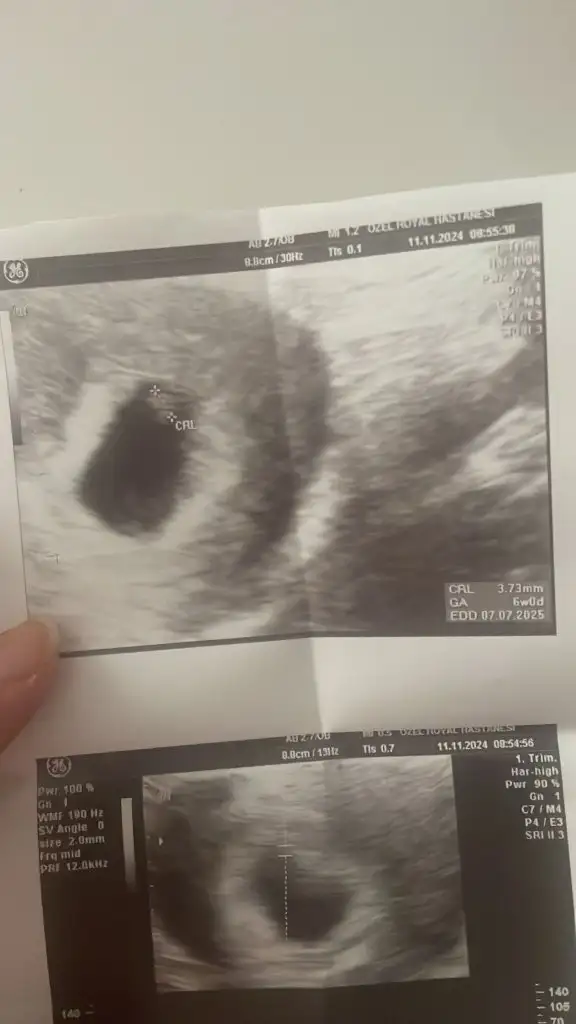

6 haftalik vajinal görüntü banada yorum yazarmisiniz? Bir kızım var bunu merak ediyorum

• IMG-20241105-WA0106.webp

IMG-20241105-WA0106.webp

25,3 KB · Görüntüleme: 41

• IMG-20241105-WA0108.webp

IMG-20241105-WA0108.webp

34,8 KB · Görüntüleme: 41